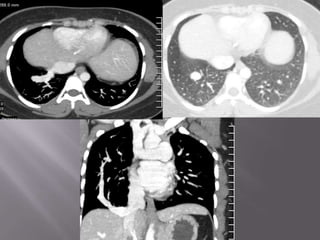

FINDINGS; 1). MASS IN LT LOWER LOBE.

2). LT HILAR & MEDIASTINAL ADENOPATHY.

3). TUMOUR INVASION OF LT ATRIUM.

4). TUMOUR INVASION OF LT PULMONARY ARTERY

ADVANCED BRONCHIAL CA